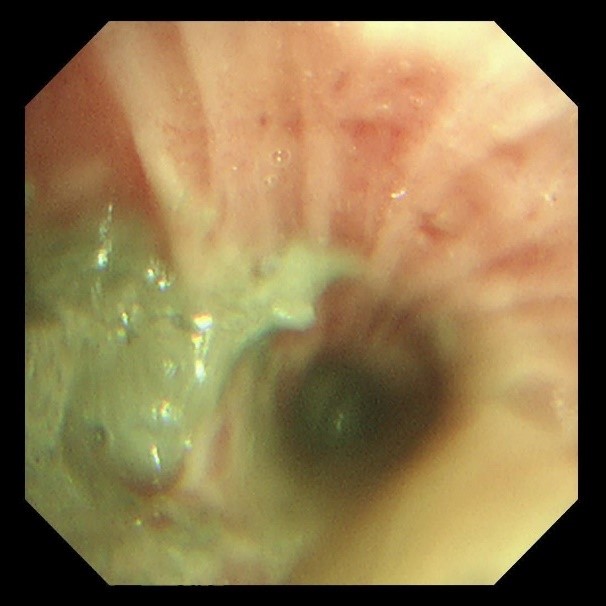

两天后复查支气管镜,发现患者左下叶背段远端细支气管仍有残留泥沙样异物。团队采用超细支气管镜联合冷冻技术,通过冷冻探头将异物凝固,再用超细活检钳逐支清理,实现对远端气道的彻底清理,实现气道“零死角”。

(超细支气管镜见左下叶背段远端支气管泥沙样物质)